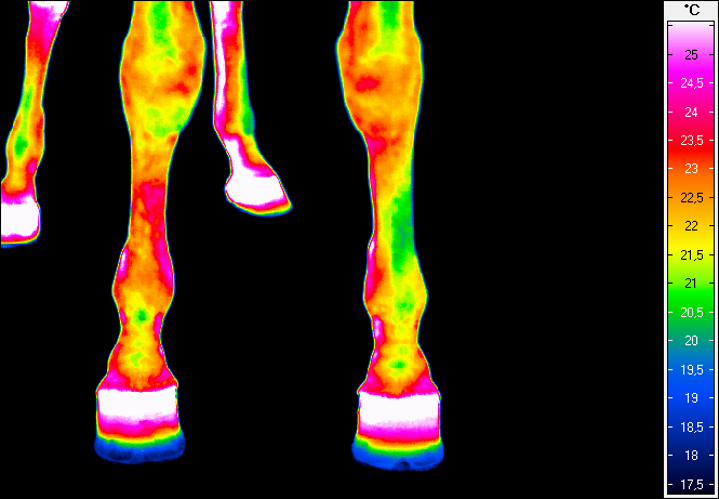

Termografia umożliwia nieinwazyjny pomiar rozkładu temperatury na powierzchni ciała konia. Wynikiem badania jest obraz – termogram, w którym poszczególne barwy odpowiadają określonym zakresom temperatur. Uzyskany rozkład cieplny odzwierciedla przede wszystkim ukrwienie tkanek powierzchownych, aktywność metaboliczną mięśni oraz właściwości izolacyjne skóry i okrywy włosowej.

W warunkach prawidłowych rozkład temperatury ciała konia charakteryzuje się wysokim stopniem symetrii pomiędzy lewą i prawą stroną. Najwyższe wartości temperatur obserwuje się w okolicach dobrze unaczynionych, takich jak oczy, nozdrza czy większe masy mięśniowe, natomiast najchłodniejsze obszary obejmują dalsze odcinki kończyn. Odstępstwa od tego wzorca – zwłaszcza asymetrie przekraczające około 1°C – mogą wskazywać na zaburzenia fizjologiczne lub rozwijające się procesy zapalne.

Interpretacja badań termograficznych wymaga uwzględnienia wielu zmiennych, które mogą wpływać na wynik pomiaru. Do najważniejszych należą warunki środowiskowe, takie jak temperatura i wilgotność otoczenia, ruch powietrza czy nasłonecznienie. Istotną rolę odgrywa również okrywa włosowa. Jej długość i gęstość mogą maskować rzeczywisty rozkład temperatur.

Równie ważne są cechy indywidualne zwierzęcia, w tym budowa ciała, poziom umięśnienia oraz aktualny stan fizjologiczny. Z tego względu badania termograficzne powinny być wykonywane w możliwie powtarzalnych warunkach, po odpowiednim okresie aklimatyzacji konia, a analiza wyników powinna opierać się przede wszystkim na porównaniach symetrycznych obszarów ciała.

W medycynie weterynaryjnej i fizjoterapii najszersze zastosowanie termografia znalazła w ocenie dalszych odcinków kończyn, które są szczególnie narażone na urazy w trakcie treningu i użytkowania sportowego.

Metoda ta pozwala na identyfikację obszarów o podwyższonej temperaturze, związanych z zapaleniem ścięgien, więzadeł, torebek stawowych czy okostnej, często jeszcze przed pojawieniem się wyraźnych objawów klinicznych. Oprócz kończyn, istotnym obszarem zastosowania termografii jest grzbiet konia. Zaburzenia w obrębie mięśni przykręgosłupowych, więzadeł nad- i międzykolcowych czy stawu biodrowo-krzyżowego często mają charakter złożony i nie zawsze są łatwe do jednoznacznego rozpoznania przy użyciu standardowych metod. Termografia umożliwia wizualizację zmian w aktywności cieplnej tych struktur, co może wskazywać miejsca przeciążenia, bólu lub kompensacji ruchowych.